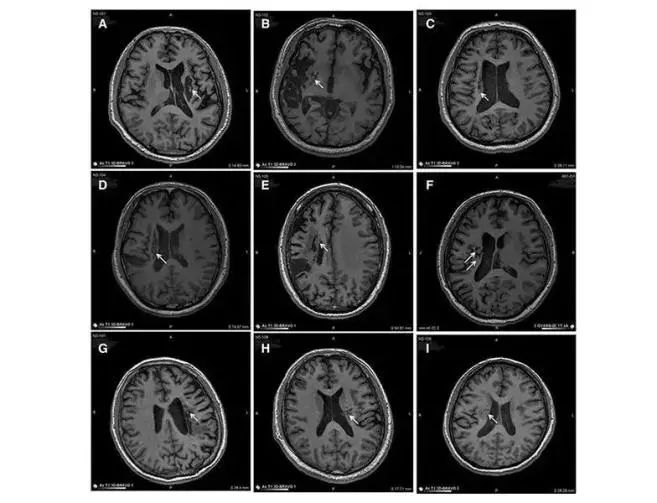

中風可導致神經元損傷。對干細胞轉運 MED 的研究表明,干細胞可以再生和修復受損的腦神經元,從而減少中風患者的后遺癥癥狀。在 9 名不同年齡的腦卒中偏癱患者中,將干細胞移植到腦梗塞區域取得了顯著的臨床效果。

9 名患者的成像顯示病變區域的組織發生了顯著變化。影像學顯示,移植到腦梗死病變中的干細胞分化為神經系統的各種細胞,分泌營養因子,促進神經和血管再生,修復受損的血腦液屏障,減少炎癥反應,促進腦梗死動物神經功能的恢復。結果,9 名臨床患者的偏癱癥狀明顯改善。